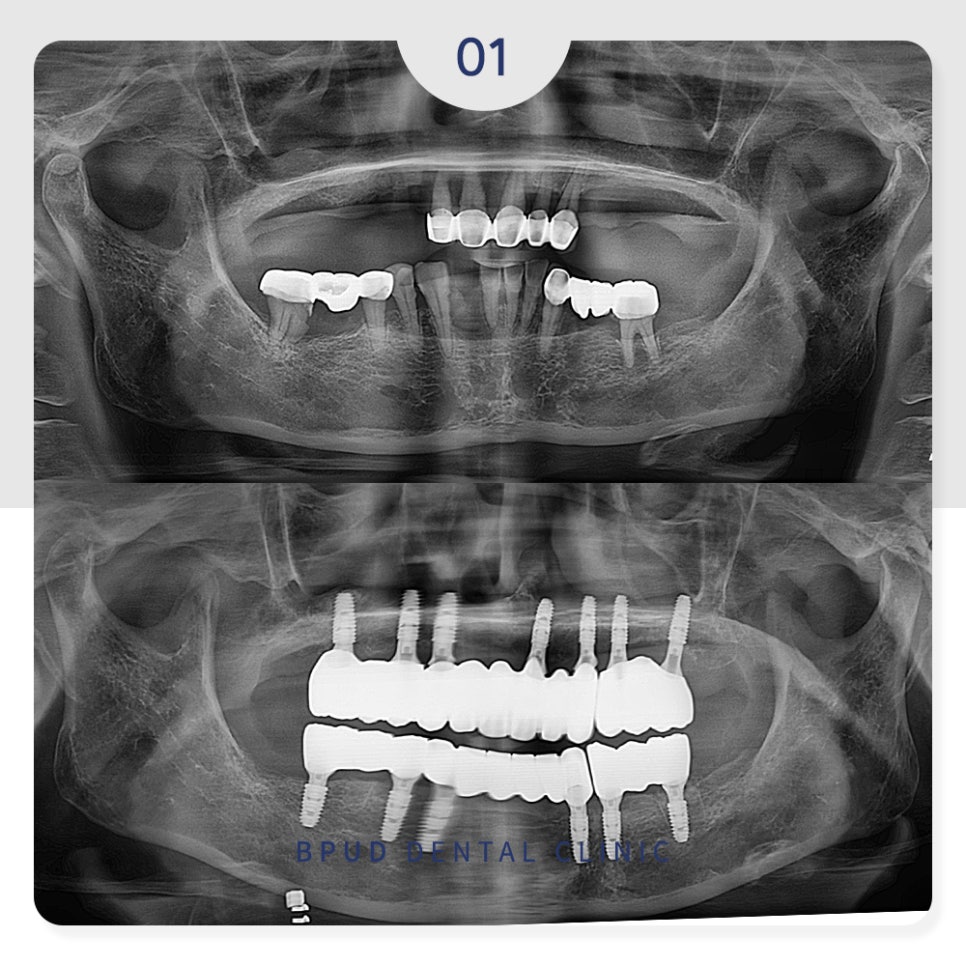

오늘은 부분 틀니를 사용하시다가

전체 임플란트로 교체하신

환자분을 소개해 드리려고 합니다.

24.01.04

이후 인공치근과 잇몸뼈가 충분히

융합될 수 있도록 4~5개월의 기간을

기다려준 후 순차적으로 보철을 완성하였습니다.

24.02.08

큰 두려움이나 통증 없이

의식하 진정요법을 통해 편안하게

마무리하실 수 있어 환자분의 만족도도

높으셨는데요.

꼈다 뺐다 해야 하는 틀니의 불편함이

없어지고 앞니도 너무 예쁘다는

말씀을 해주셨습니다.